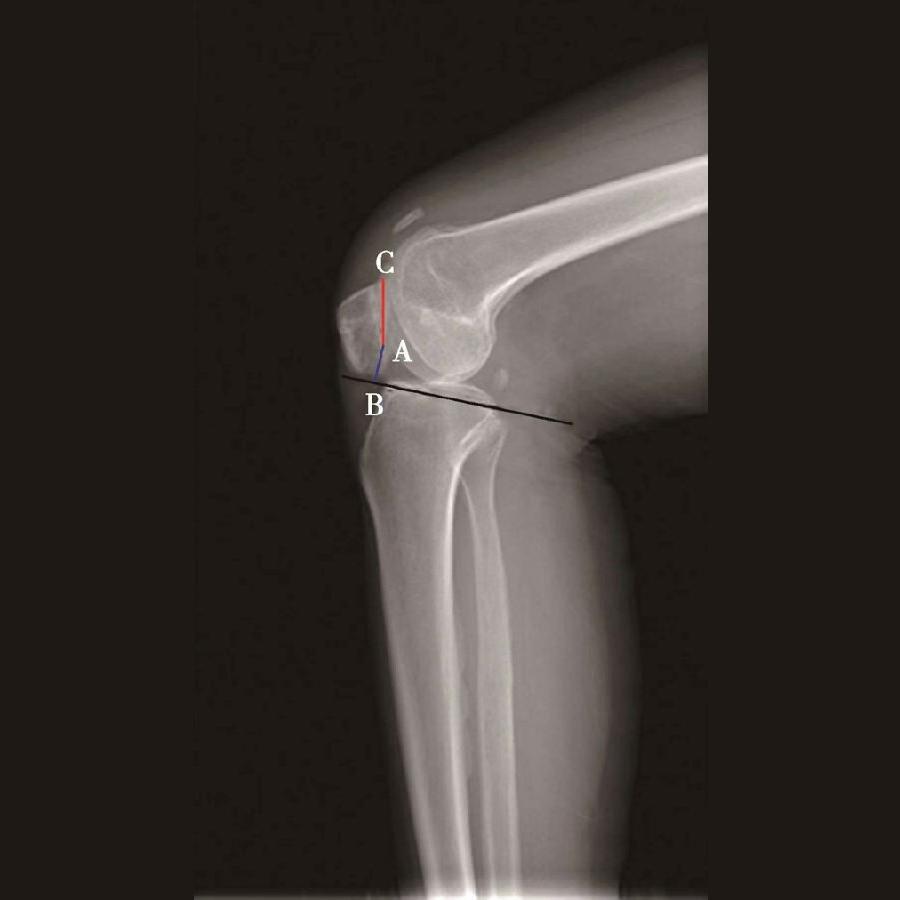

体位:侧卧位屈膝30°。

如图示:AB为髌骨关节面最低点到胫骨平台轮廓前上角最短的距离,AC是髌骨关节面的长度。Caton指数=AB/AC(图1)。

图1

图2 Caton指数=AB/AC=1.10,为正常髌骨高度

临床工作中常常使用其来估计胫骨结节移位的效果。正常人的Caton指数=1,正常范围0.8~1.2(图2)。需要注意的是:术前规划胫骨结节需要移位的理论距离为AB-AC,这就是需要将胫骨结节向远端移位的最大距离。但在术中胫骨结节转移的距离往往要小于这个距离,避免因过度移位造成医源性的低位髌骨。